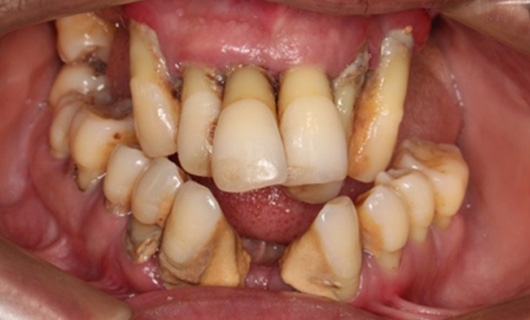

Dentures that are supported by an implant can provide significant improvements in chewing and smiling. In contrast to regular complete dentures, these dentures are horseshoe-shaped reducing bulkiness and creating more space on the palate for better tasting ability. A person with implant-supported dentures can enjoy fruits, vegetables, steaks, corn on the cob, and other foods compared to a person wearing traditional dentures. In addition, implant-support dentures significantly boost patients’ confidence to smile and speak.